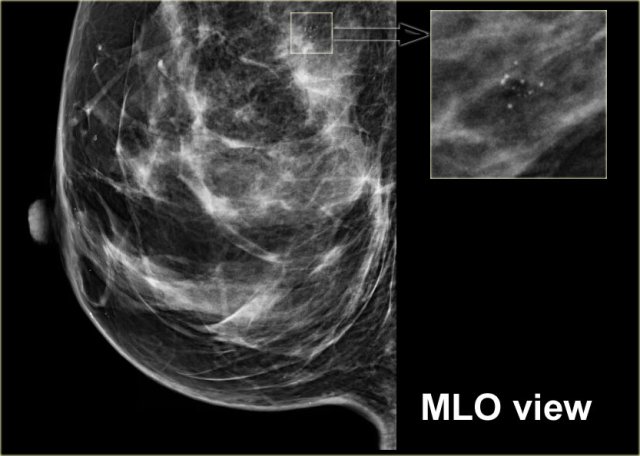

Here another example of the tatoo-sign.

First notice that there are some calcifications that are clearly located within the skin (arrows).

The cluster calcifications on the MLO-view has the exact configuration as the cluster on the CC-view (next image).

On the CC-view the configuration of the microcalcifications is exactly the same.

If these calcifications were located in the centre of the breast they should have a different configuration, because the projection is different.

Only when calcifications are located within the skin their configuration stays the same.